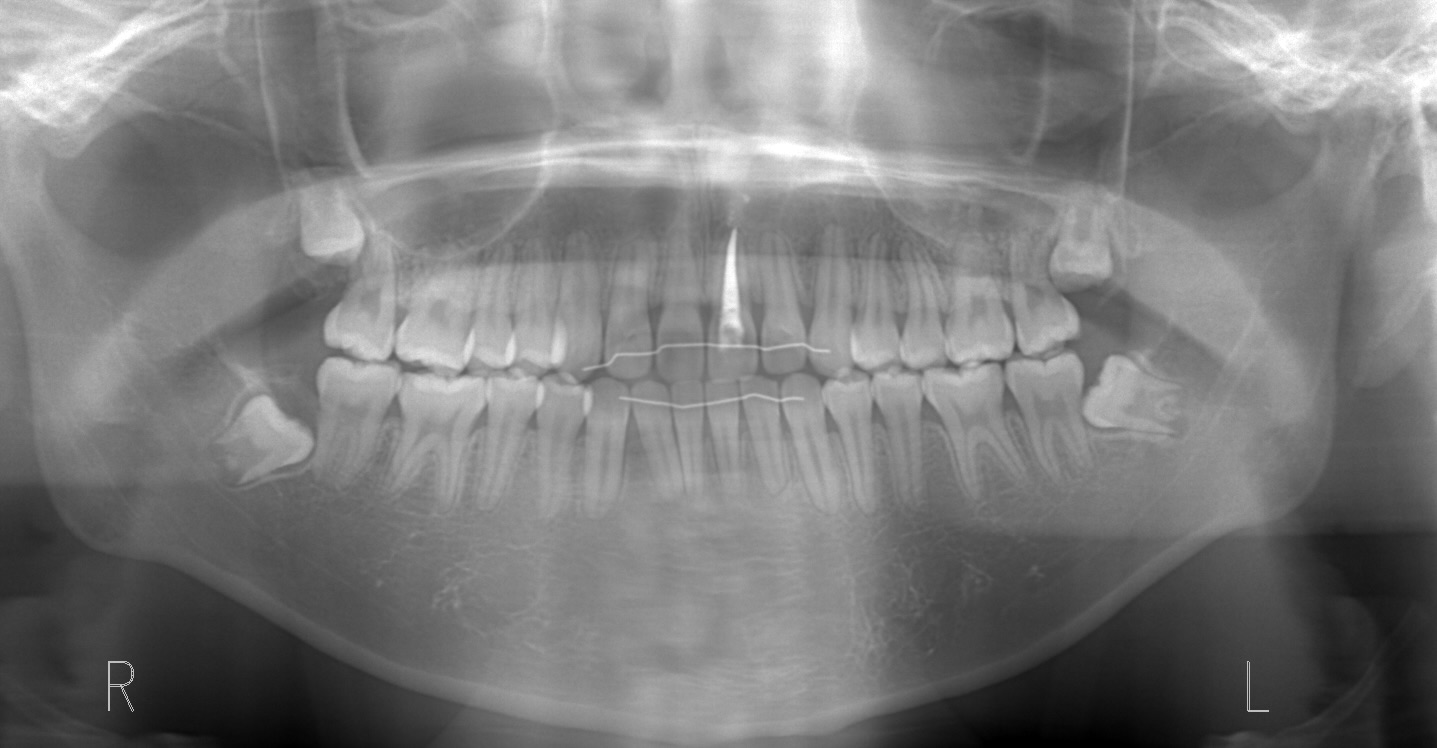

セファロレントゲンにより親知らずの存在を確認するも13歳でありすぐに抜歯することは不可能と判断。

親知らずが抜ける位置まで移動してきたため、矯正治療しながら親知らずの抜歯も行う。

親知らずに押され臼歯部での噛み合わせが高くなってしまい、前歯が噛まなくなってしまっている。

親知らずを抜歯してそのスペースを利用して臼歯部を圧下しつつ、前歯の噛み合わせを近づけていく。